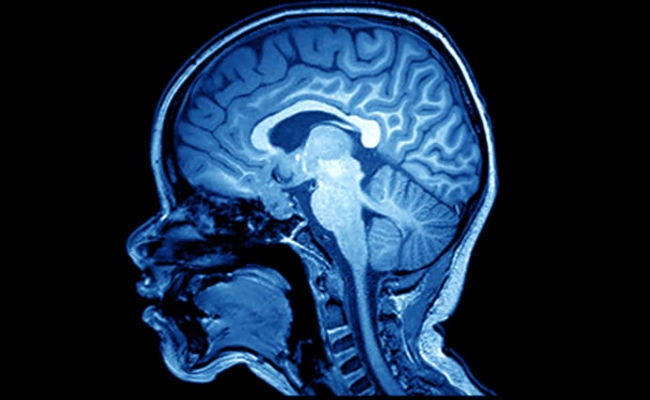

मस्तिष्क स्कैन दिमागी और मानसिक विकृति का पता लगाने में कर सकता है मदद

वाशिंगटन : वैज्ञानिकों का कहना है कि मस्तिष्क का ऐसा स्कैन जो यह दिखाता है कि मस्तिष्क के क्षेत्र किस प्रकार परस्पर प्रभाव डालते हैं इससे माइग्रेन , तनाव , बायपोलर विकार सहित मस्तिष्क से संबंधित कई अन्य बीमारियों का पता लगाने में मदद मिल सकती है.

‘न्यूरॉन’ जर्नल में प्रकाशित एक अध्ययन के अनुसार फंक्शनल कनेक्टिविट एमआरआई ( एफसीएमआरआई ) नाम का स्कैन किसी व्यक्ति का मस्तिष्क किस प्रकार से बंधा है इसमें आसानी से मूल अंतर का पता लगाने में सक्षम है. यह एमआरआई विश्वसनीय है.

स्वस्थ व्यक्ति और मस्तिष्क की बीमारियों से ग्रसित व्यक्ति के बीच अंतर पता करने की क्षमता भी इस तकनीक के पास है. वाशिंगटन यूनिवर्सिटी स्कूल ऑफ मेडिसिन की प्रोफेसर स्टीवन पीटरसेन ने बताया , ‘ यह फंक्शनल क्नेक्टिविटी एमआरआई के महत्व बताने की तरफ बढ़ाया गया कदम है.’

पीटरसेन ने बताया , “इससे पहले कि हम एफसीएमआरआई के आधार पर बीमारी का इलाज शुरू करें , हमे यह पता होना चाहिए कि यह वास्तव में क्या माप रहा है. हम यहां दिखाते हैं कि यह वह नहीं माप रहा है जो आप सोच रहे हैं बल्कि यह इस बात की माप कर रहा है कि आपका मस्तिष्क कैसे बना हुआ है. इस बात ने क्लिनिकल जांच के नए दरवाजे खोल दिए हैं.”